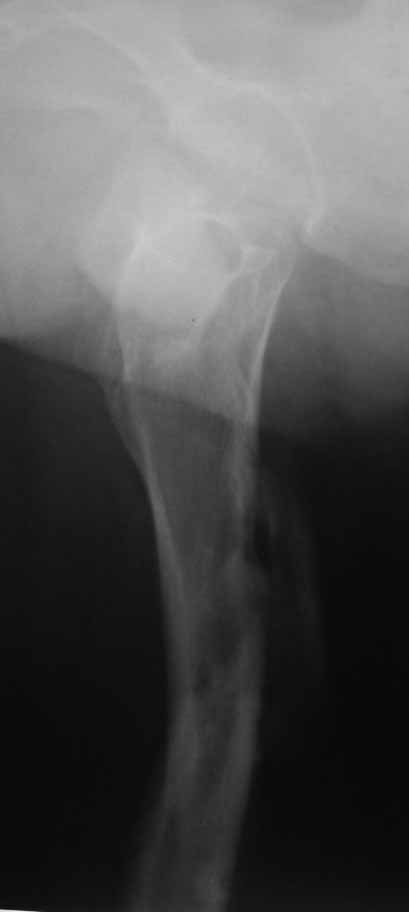

[Ortho] неправильно сросшиеся перелом бедренной кости

Уважаемые коллеги, доброго времени суток. Молодой парень 30 лет, в 2010г получил травму в

результате ДТП.

Лечили на скелетном вытяжени 6 нед с последующим наложением кокситной

повязки на 12 нед. От предложенного остеосинтеза пластинами воздержался( БИОС к сожалению

пока не доступен) В настоящее время ходит заметно прихрамывая, левая нижняя конечность

укорочено сравнительно на 3,0 см.Объем движений в суставах полное. Как можно помочь

больному в дальнейшем. Буду рад Вашим советам. Спасибо.